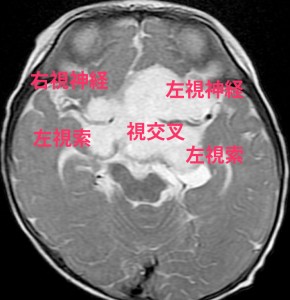

視路 optic pathwayの解剖学

- 視覚情報は,眼球網膜に入って,眼窩内の視神経を通って,頭蓋内に入ります

- 頭蓋内視神経はとても短いです

- 両側の視神経が交わる所を視交差とよびます

- 視交差からまた左右に分かれて,視索になります

- 視索は外側膝状体というところで脳の中に入ります

- そこからは内包後脚,視放線を伝わって,後頭葉まで行きます

- 視路毛様細胞性星細胞腫は上記のどこでも発生します

- この視路に沿って浸潤して広がります